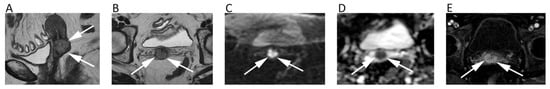

2. Neuro

3. Head and Neck

4. Chest

10. Urinary System and Adrenal

11. Prostate